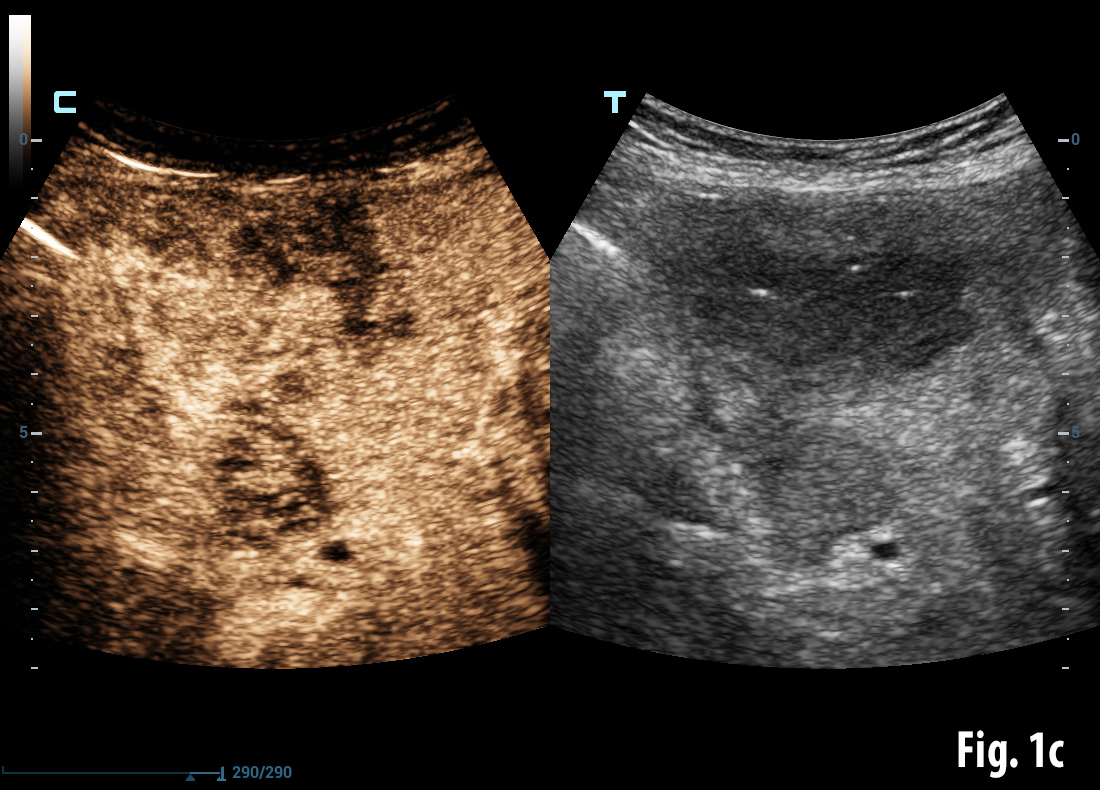

Conventional B-mode ultrasound revealed a mass lesion in the gallbladder region (a) and air bubbles within the liver (aerobilia) (b). Contrast enhanced ultrasound showed arterial enhancement as a sign of neoplasia (c). Endoscopy revealed a gallstone in the duodenal bulb (d). Elastography showed stiff tissue (blue) supportive of neoplasia (e). Details of elastography are explained in the EFSUMB guidelines on elastography [(1, 2)].

![Bouveret syndrome</br> [Apr 2016]](http://s834315022.websitehome.co.uk/wp-content/uploads/2020/11/cotm_april2016-fig1c.jpg)